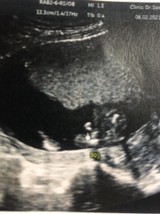

ช่วยดูให้หน่อยค่ะว่าผู้ชาย100%มั้ยคะแม่แอบหวังผู้หญิง555555

ชัดเหมือนกันเลยค่ะแม่😅😅 อะจู๋โด่มาเลย

กำลังตั้งครรภ์